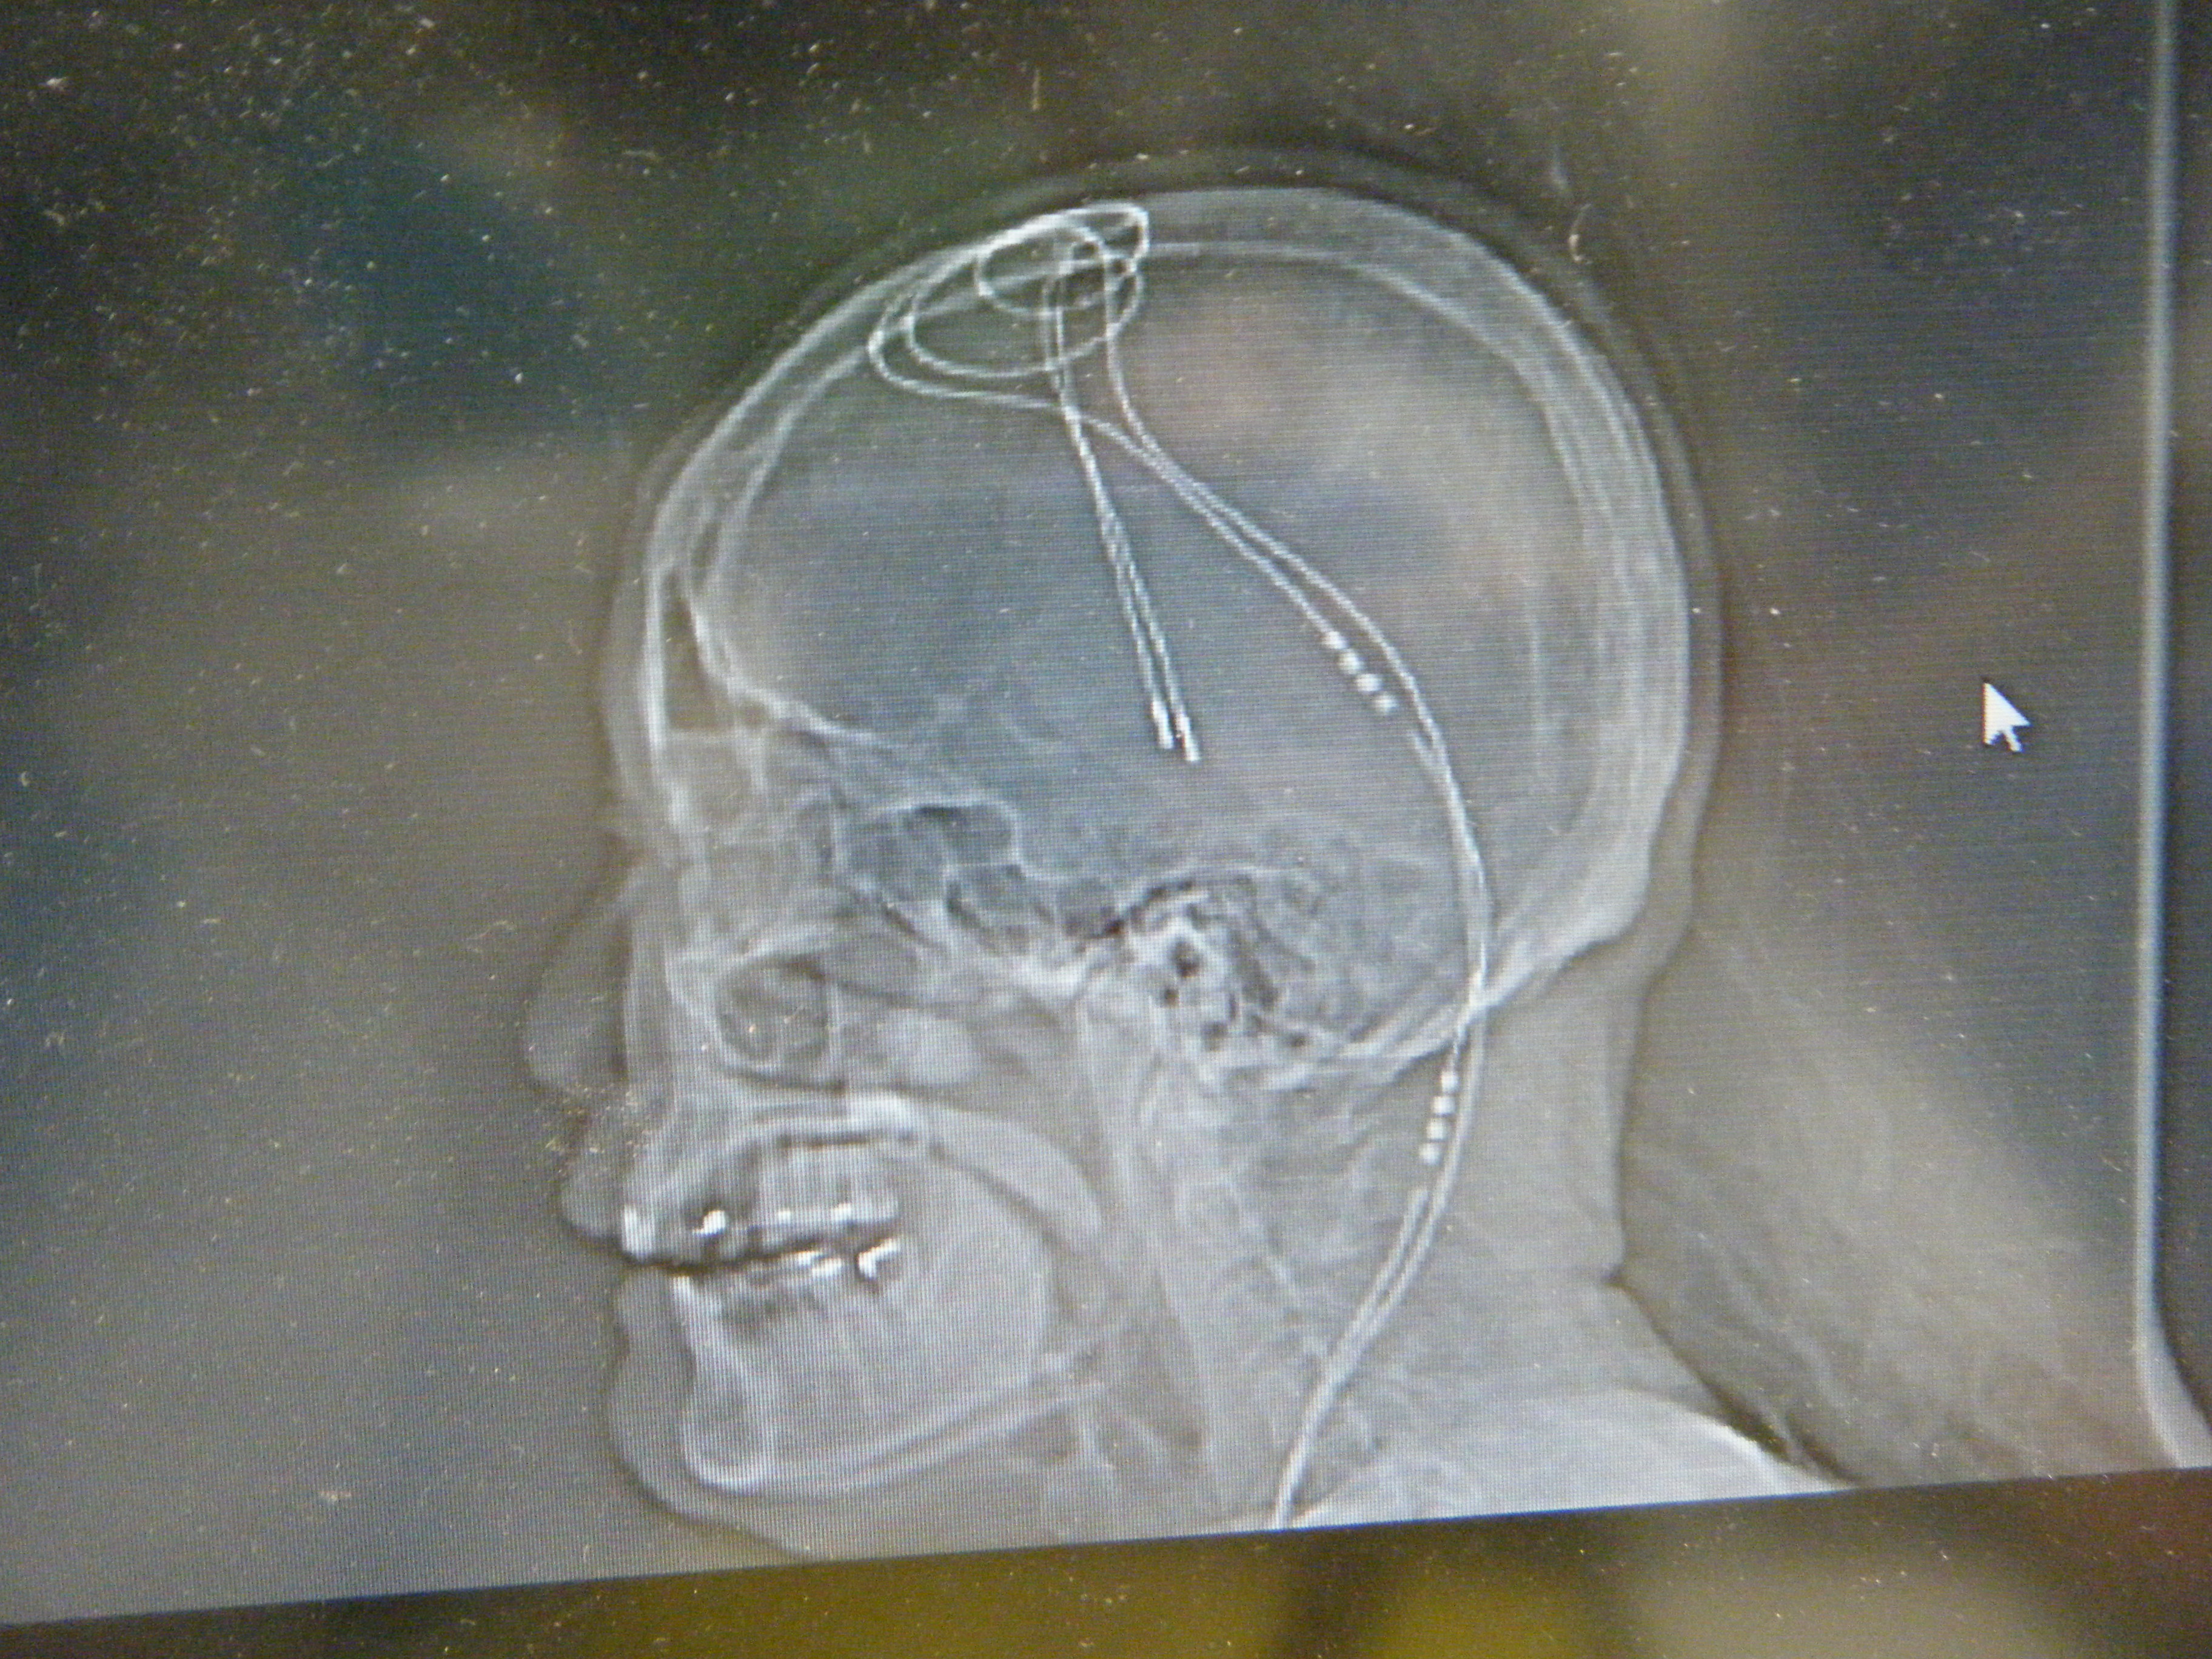

患者的腦部X-RAY(家屬口中的蟑螂鬚鬚!)

當患者到達急診室後,家屬跟急診室醫生告知病史時,提到了DBS,當下兩位

值班醫師都對此手術沒有印象,只好送患者去照X-RAY,我也想知道到底是什麼手

術,到底蟑螂的鬚鬚是啥?結果在X光及CT後一覽無遺,原來是這樣的一個手術,利

用調節器經過導線來調節大腦的電流(簡單來說應該是這樣).這種手術或許不常見,

DBS手術包括了植入一個細長的電極導線(electrode),至腦中的丘腦下核(subthalamus nucleus,STN)或是蒼白球內核(globus pallidus internal segment,GPi),此一導線經皮下和植入於胸前的脈衝產生器(pulse generator)相連(此一裝置,類似於心律調節器)。不同於燒灼手術,DBS不會破壞腦部組織,它是一種可逆式的反應,藉著產生電流來控制調節腦內不正常的活動訊息,而達到運動症狀的控制。目前DBS已成為治療巴金森氏病最有效的手術方式,但它也是非常複雜及精細的一種手術。此外,在達到它的效果之前,病人必須經過一段調適期及有耐心的等待。